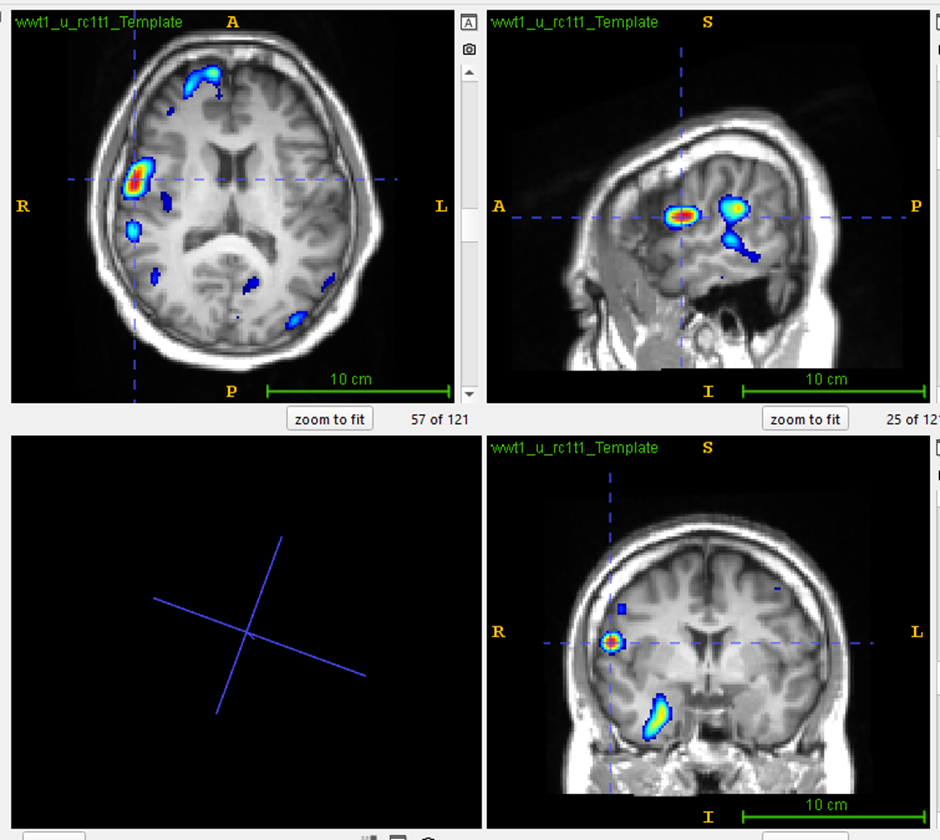

Case Study 03:

Posterior cortex

epilepsy

MRI Scan

Visual analysis: PET scan of a patient with drug-resistant temporal lobe epilepsy showed bilateral temporal lobe hypometabolism.ent.

PASCOM: Focal hypometabolism was localized to right hippocampus and temporal pole cortex.